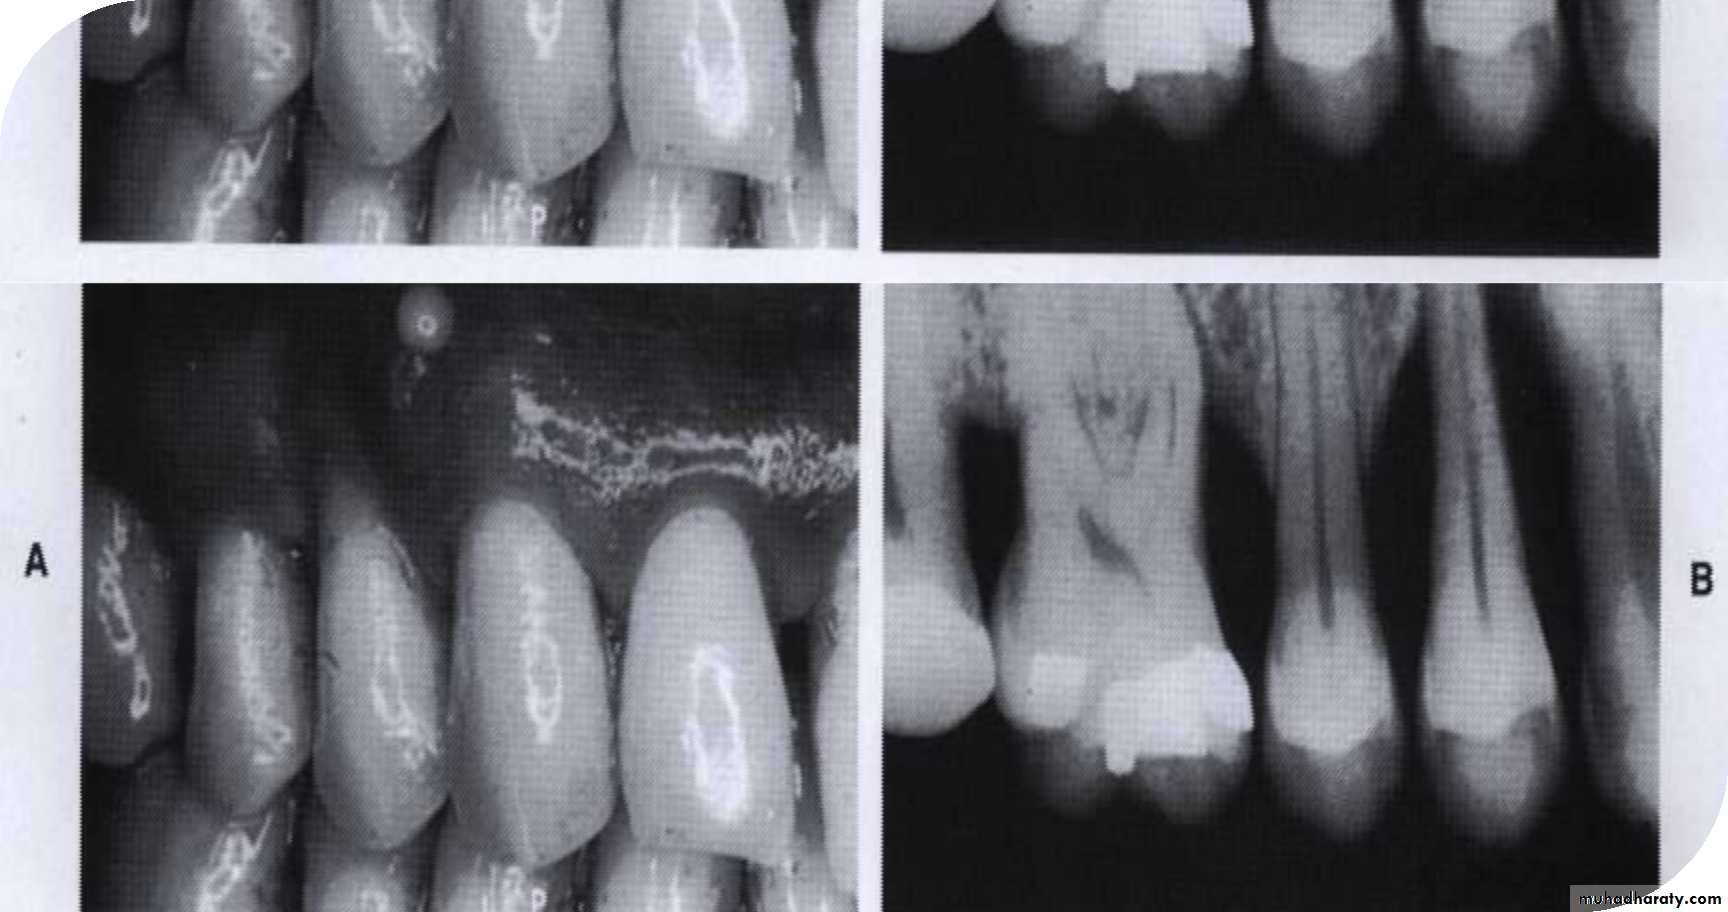

• Extrusion of the maxillary left central incisor and diastema

• associated with a periodontal pocket• Deep periodontal pocket revealed by probing. The probe has penetrated to its entire length.